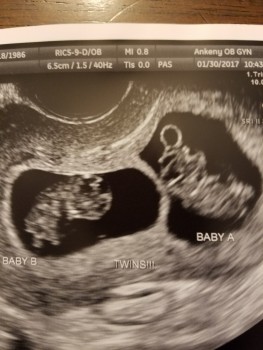

I was like that too, after all I was 9 week along with TWINS! My husband and I went to my first OB appointment together. This was our third pregnancy. Our first two children were still very young but we wanted one more addition to our family. To say we were shocked to be having twins was an understatement. We left the OB appointment with so many scenarios to consider. How were we going to arrange the kids’ rooms? Could we handle fours kids? We started planning. We went minivan shopping that afternoon as we would defiantly need a larger vehicle, but how were we going to arrange four car seats? We called our immediate family and shared the news (they didn’t even know we were expecting). They were shocked. We told a few close friends and specifically friends of twins. We needed support and advice. Were we going to survive? Yes, they reassured us. I had the perfect social media post pictured in my mind and ready to share. As the weeks passed I had an idea how I was going to handle my career and juggling 4 small children. Our mindset shifted from shock to being ready to take on the challenge. I was excited to take on the challenge that not many women get the opportunity to.

Three weeks after receiving the news of expecting twins we went to our first perinatal appointment as I was now considered high-risk. We took the other two kids to daycare and my husband and I had a full day planned to continue preparing. More minivan shopping, installing a swing set in the backyard to occupy the kids and finalizing some much needed house projects. During the ultrasound we saw Baby A move and kick around. The ultrasound tech took pictures and measurements. Baby was measuring 12 weeks 1 day. Then we got the dreaded news. Baby B did not have a heartbeat. Growth had stopped at 11 weeks 5 days. Just days before our appointment. I believe a piece of my heart died that morning in the ultrasound room. I knew that there is always risk of losing a baby in the first trimester and one in four women experience a miscarriage but you never imagine it happening to you. After returning to our regular OB he was just as shocked as us. There was no sign of irregular growth at 9 weeks and miscarriages later in the first trimester are less common.